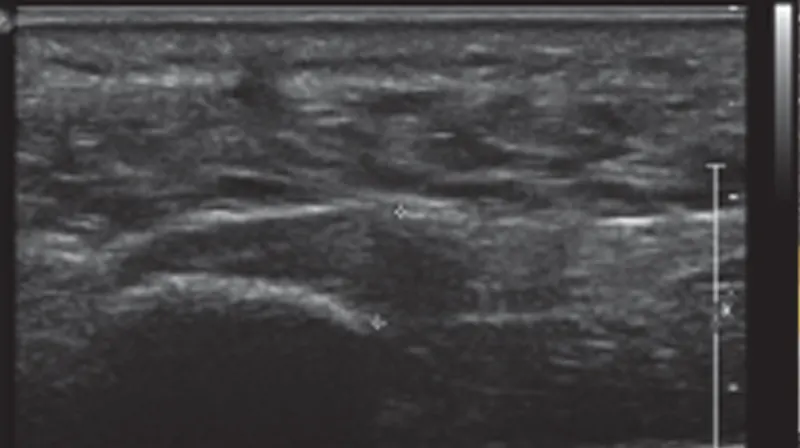

Ultrasounds... of the Feet?

February 2019

My Stomach Hurts - Could it be Gallstones?

December 2015